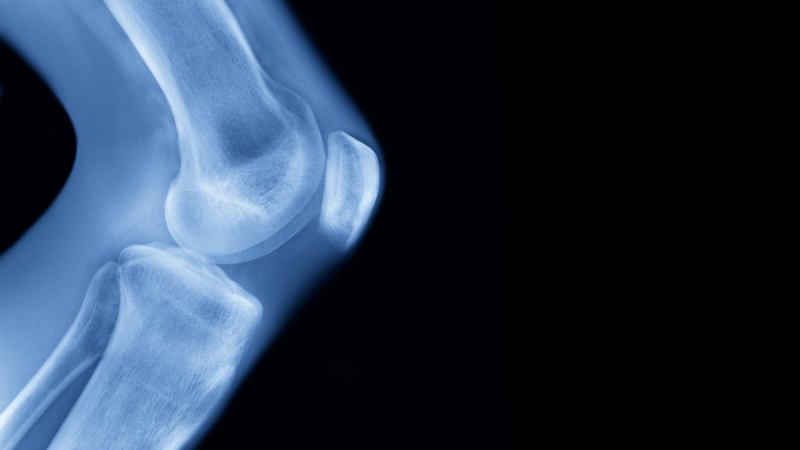

The doctor’s name is Kevin Debiparshad, and he is the founder of LimbplastX, the clinic that performs a leg-lengthening procedure in which titanium pins are implanted into the intramedullary canal of the bone to make it longer. Though it’s a serious surgery, it can usually be achieved with one one-inch incision and three 1/2-inch incisions for femur lengthening. Tibial lengthening, which must be done later if the patient wants to grow up to six inches taller, requires two additional small incisions to implant the device.

The operation involves having to fracture the femur to insert the pins and extend them a tiny amount each day using a magnetic system until the desired height (three to six inches) is reached. The process takes about a year from start to finish, then the pins are removed at an additional cost of $14,000 to $20,000.